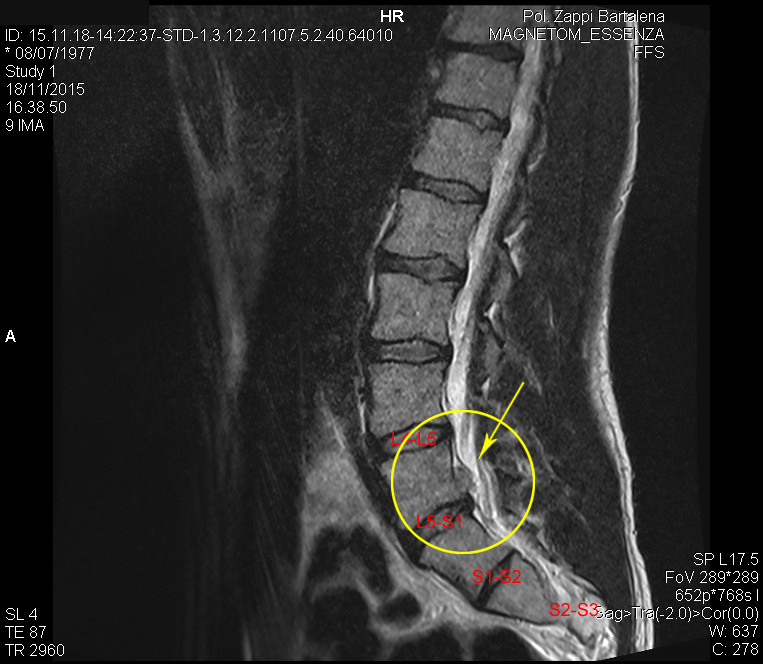

Finito il "mea culpa", veniamo alla realtà... circa 8 settimane fa mi sono procurato questa bella ernia, come si vede dalla rmn fatta la settimana scorsa.

Dalla quarta settimana ho cominciato a pensare che non era più il caso di ignorare la situazione, sono andato dal fisioterapista che mi ha sistemato un po', ma nel frattempo non ho smesso di fare stacchi e squat perché mi sentivo "bene", non sò come dire... l'unico grosso problema lo avevo facendo gli stacchi, bastava un microsecondo di distrazione per sentire una gran scossa partire da lì... L5-S1... e così mi sono deciso a fare sta risonanza:

Finito il "mea culpa", veniamo alla realtà... circa 8 settimane fa mi sono procurato questa bella ernia, come si vede dalla rmn fatta la settimana scorsa.

Dalla quarta settimana ho cominciato a pensare che non era più il caso di ignorare la situazione, sono andato dal fisioterapista che mi ha sistemato un po', ma nel frattempo non ho smesso di fare stacchi e squat perché mi sentivo "bene", non sò come dire... l'unico grosso problema lo avevo facendo gli stacchi, bastava un microsecondo di distrazione per sentire una gran scossa partire da lì... L5-S1... e così mi sono deciso a fare sta risonanza: